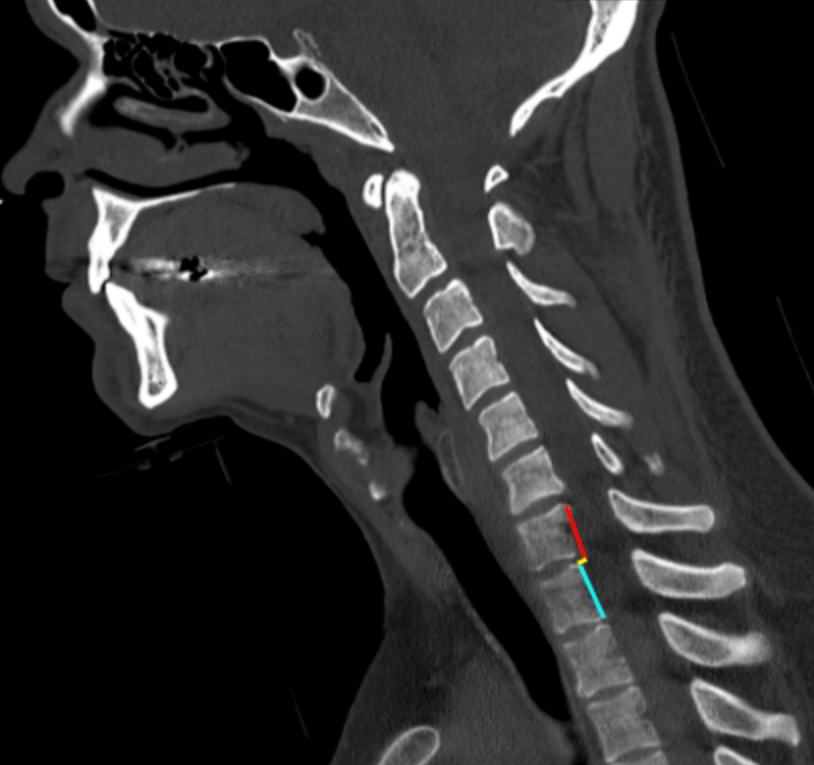

Translation on Sagittal Reconstruction

Translation on sagittal reconstruction quantifies the anteroposterior displacement of one cervical vertebral body relative to an adjacent vertebra on sagittal CT images. It is a direct indicator of spinal instability and reflects disruption of the anterior and/or posterior ligamentous complexes, often in the setting of trauma.

This measurement is particularly useful for identifying subluxation, fracture–dislocation, and unstable injury patterns, and it complements facet-based assessments (facet overlap, facet step-off) and global alignment lines.

• On the sagittal image:

• Identify the posterior cortical margin of the inferior vertebral body (reference vertebra).

• Identify the posterior cortical margin of the superior vertebral body (translated vertebra).

• Draw two vertical reference lines parallel to the sagittal axis:

• One along the posterior margin of the inferior vertebral body.

• One along the posterior margin of the superior vertebral body.

•  Measure the horizontal distance (mm) between these two lines.

• This distance represents anteroposterior translation at that level.